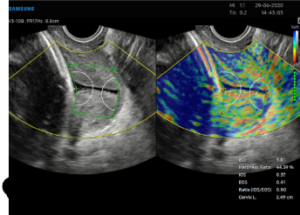

Cervical elastography is an advanced ultrasound technique that evaluates the stiffness (elasticity) of the cervix. Unlike a routine ultrasound, elastography provides quantitative information about cervical tissue, helping doctors assess conditions related to pregnancy, infertility, and cervical disorders with greater precision.

By measuring how soft or firm the cervical tissue is, elastography offers valuable insight into:

Preterm labor risk — Softening of the cervix before term may indicate early labor.

Cervical insufficiency — Detecting weakness in cervical structure early helps guide management.

Fertility assessments — Evaluating cervical tissue quality can assist in infertility workups.

Post-treatment monitoring — After cervical surgery or procedures, elastography helps assess recovery and tissue response.